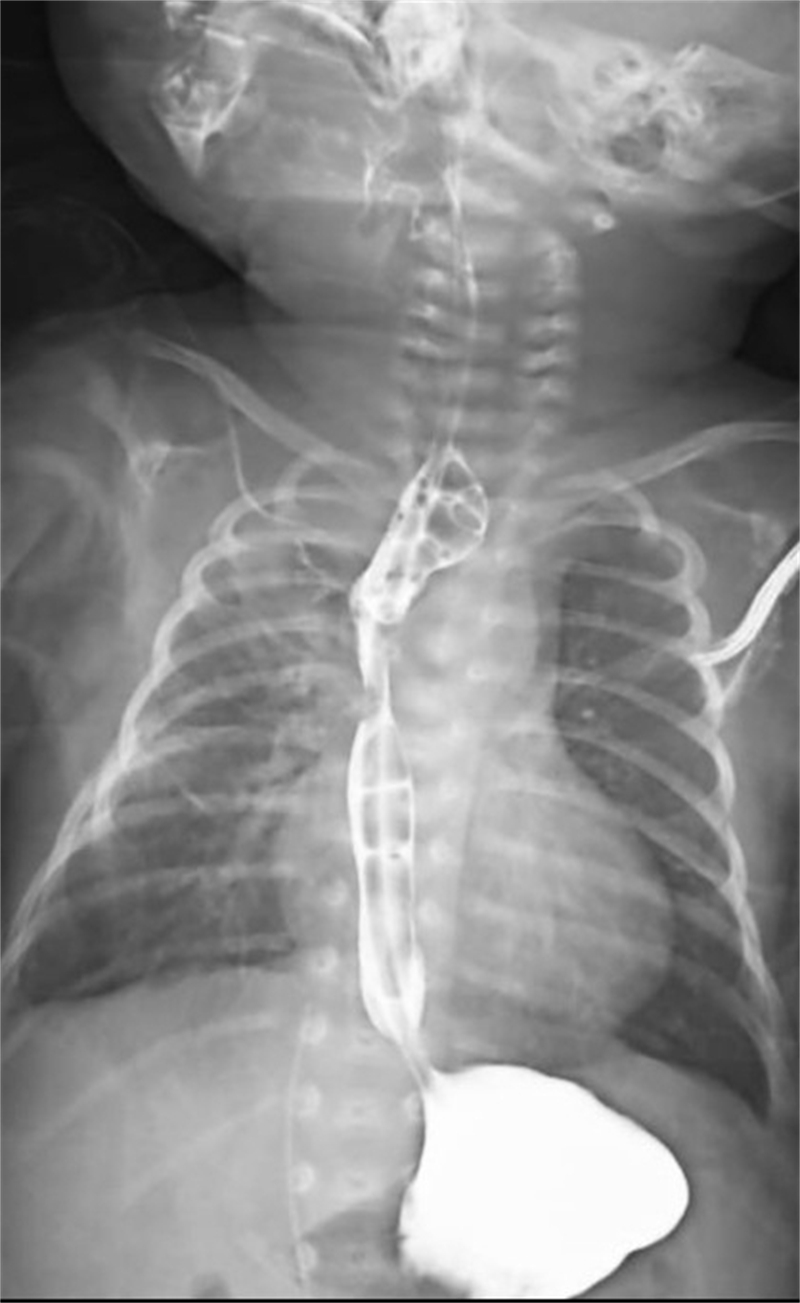

面對這一突發(fā)情況,經(jīng)驗豐富的新生兒科醫(yī)生立即警覺:萱萱有可能患有少見且嚴重的新生兒先天性疾病——食管閉鎖。為了盡快明確診斷,新生兒科與小兒外科討論后,緊急聯(lián)系放射科為萱萱安排了消化道造影、CT掃描等全面檢查。最終,檢查結(jié)果明確診斷:先天性食管閉鎖Ⅲ型伴食管氣管瘺。

前路雖難,行則將至。面對萱萱父母的信任,各科室通力合作、齊心協(xié)力,目的只有一個:讓萱萱得到及時而優(yōu)質(zhì)的治療。新生兒科細致地進行圍術(shù)期準(zhǔn)備,麻醉科精準(zhǔn)地設(shè)計麻醉方案,小兒外科選擇了操作難度高、但術(shù)后并發(fā)癥更少的“胸膜外入路”手術(shù)方案。最終,只有3天大的萱萱,順利接受了歷時1小時30分鐘的“經(jīng)胸膜外入路食管閉鎖端-端吻合術(shù)”,術(shù)后轉(zhuǎn)回新生兒科開始后續(xù)的監(jiān)護治療。

術(shù)后僅1天,萱萱便能通過留置胃管接受腸內(nèi)營養(yǎng)支持。在新生兒科醫(yī)護人員的精心照料下,術(shù)后3周復(fù)查消化道造影顯示手術(shù)切口愈合良好,萱萱終于可以自己吃奶啦!